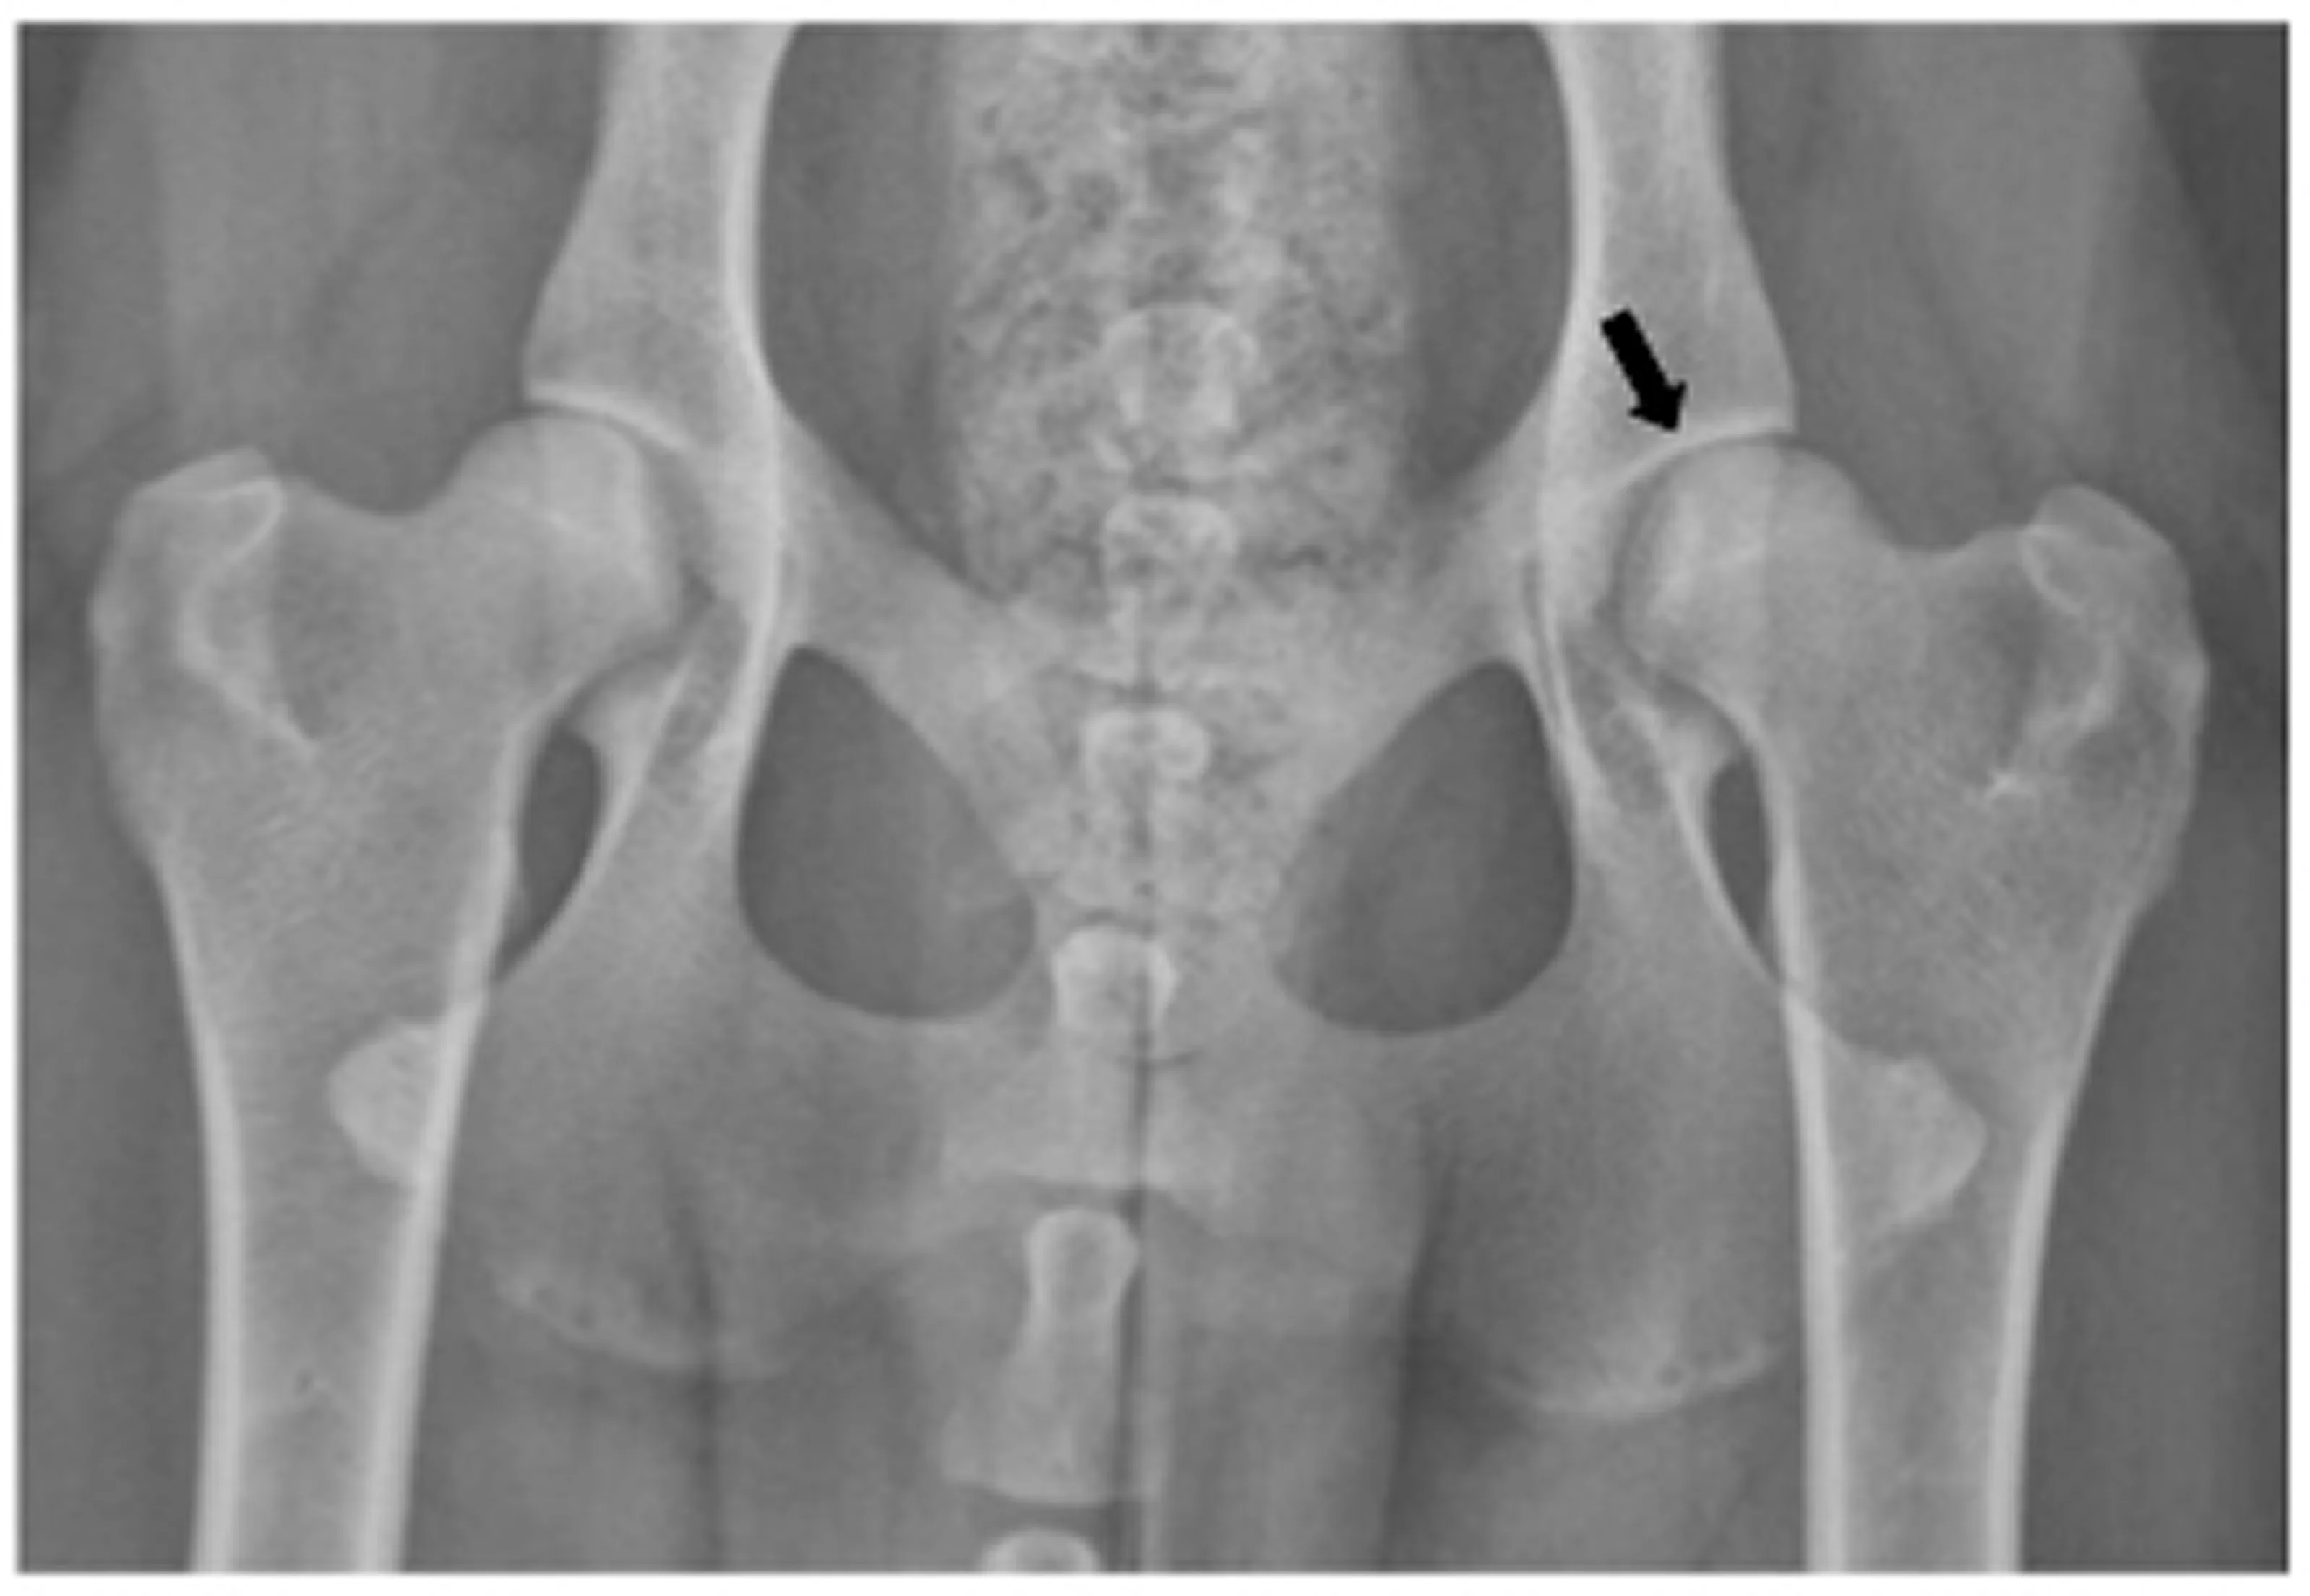

Hip dysplasia isn't just about genetics or bad joint structure…

Yes, those things matter.

But here's what's really causing your dog's pain:

But when hip dysplasia sets in, that loose hip socket creates abnormal friction. And that friction triggers inflammation.

Everything we're taught to prescribe in vet school only addresses half the problem.

NSAIDs like Rimadyl or Carprofen reduce the inflammation and pain. Which is great…

In the short term.

But they do absolutely nothing to rebuild the cartilage or restore the joint fluid that's been destroyed.